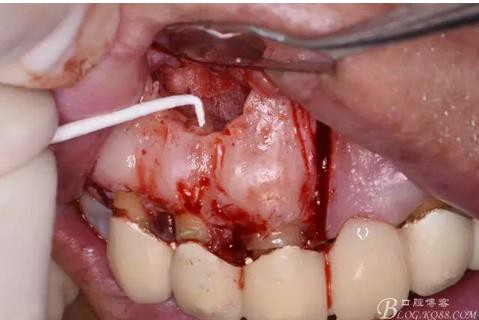

圖11.摘除囊壁后形成的骨腔

圖12.超生骨刀切除12根尖